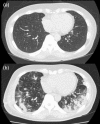

Chondrosarcomas are the most frequently occurring primary malignant chest wall tumors. Furthermore, the lungs serve as the most frequent sites for metastases. Pulmonary metastases from sarcomas usually appear as round nodules of varying sizes on roentgenograms. Here, we report an unusual clinical and radiographic presentation of pulmonary metastasis from a costal chondrosarcoma. Bilateral pulmonary metastases developed soon after wide surgical resection. Thoracic computed tomography revealed unusual radiological findings: consolidation accompanied with ground-glass opacity. To confirm the metastasis, we recommend a transbronchial biopsy in cases where unusual pulmonary findings are detected.